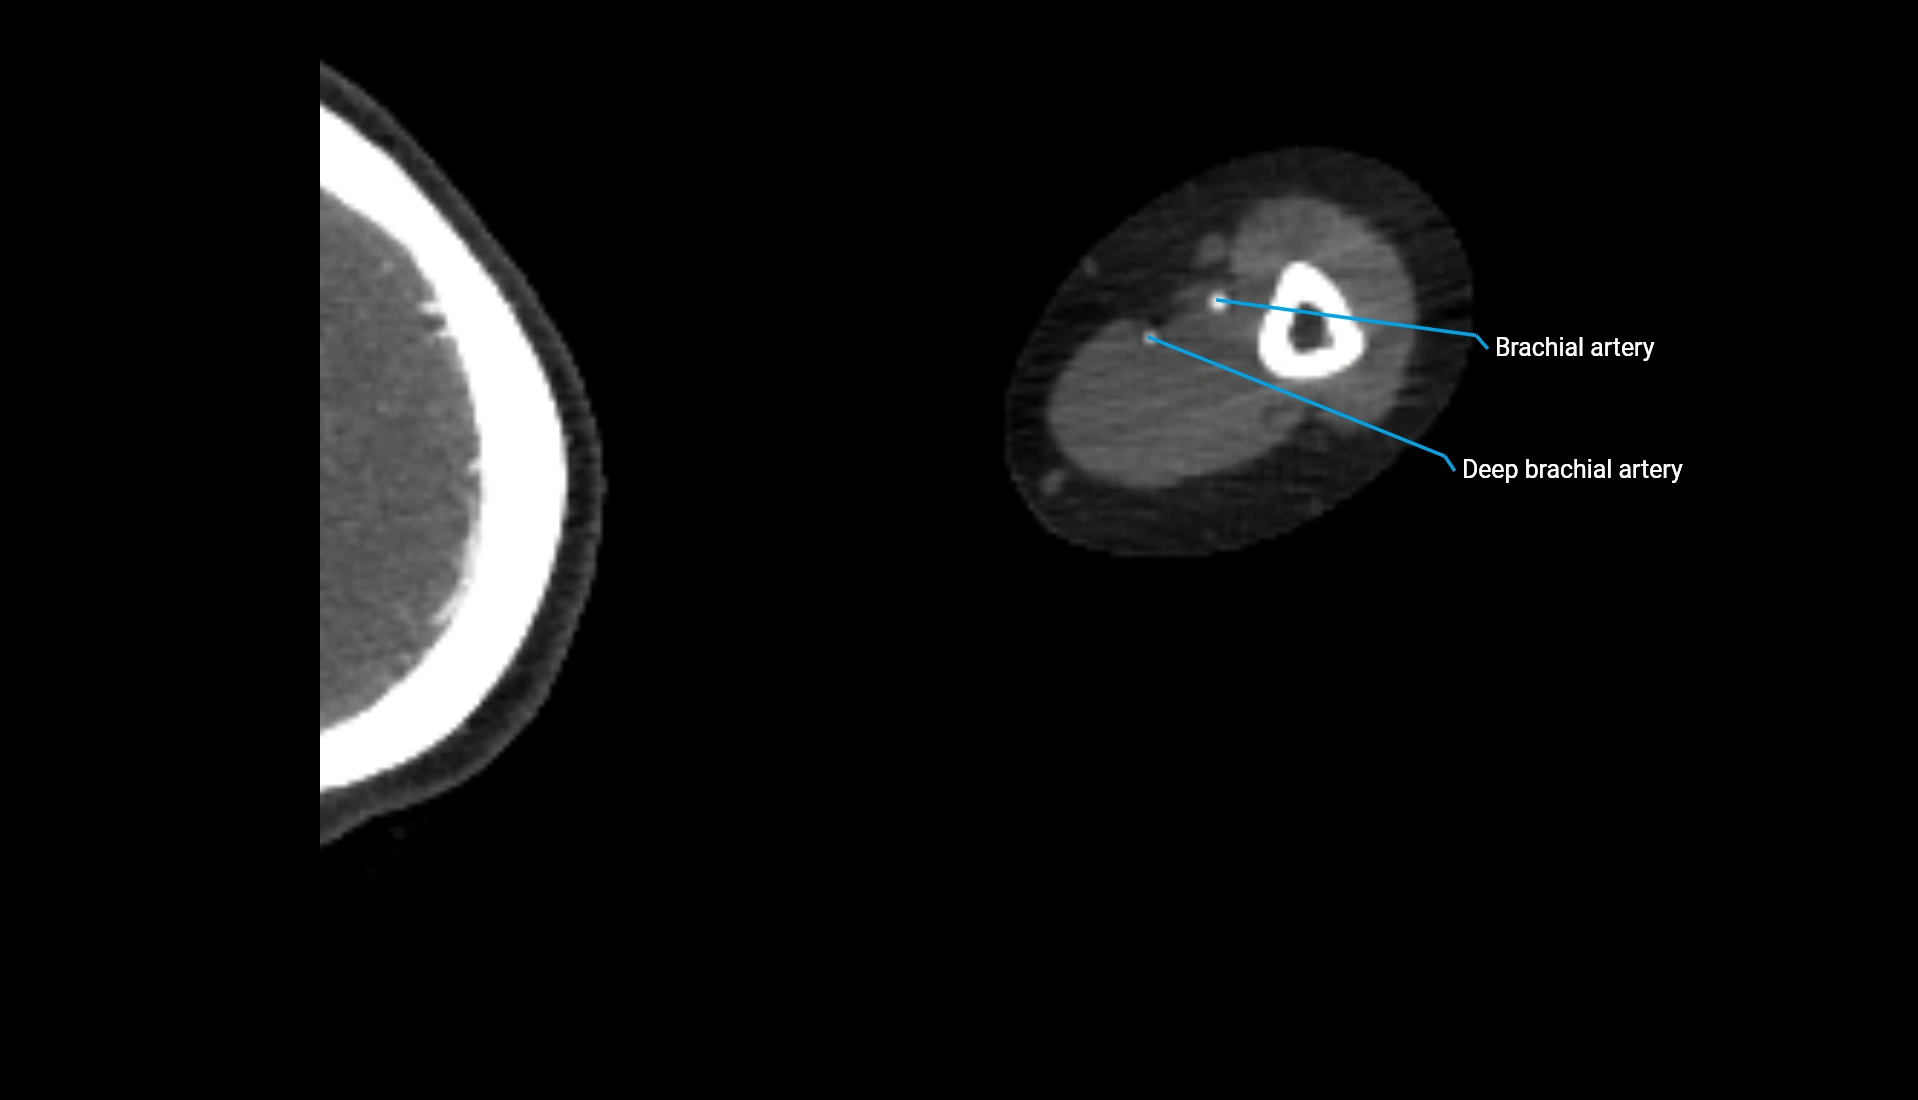

CT Appearance

Non-Contrast CT:

• Cortex: High-density, sharply defined

• Subchondral bone: Dense cancellous matrix

• Articular surface: Smooth concave contour articulating with the capitellum

• Excellent for evaluating bone integrity, alignment, and subtle fractures